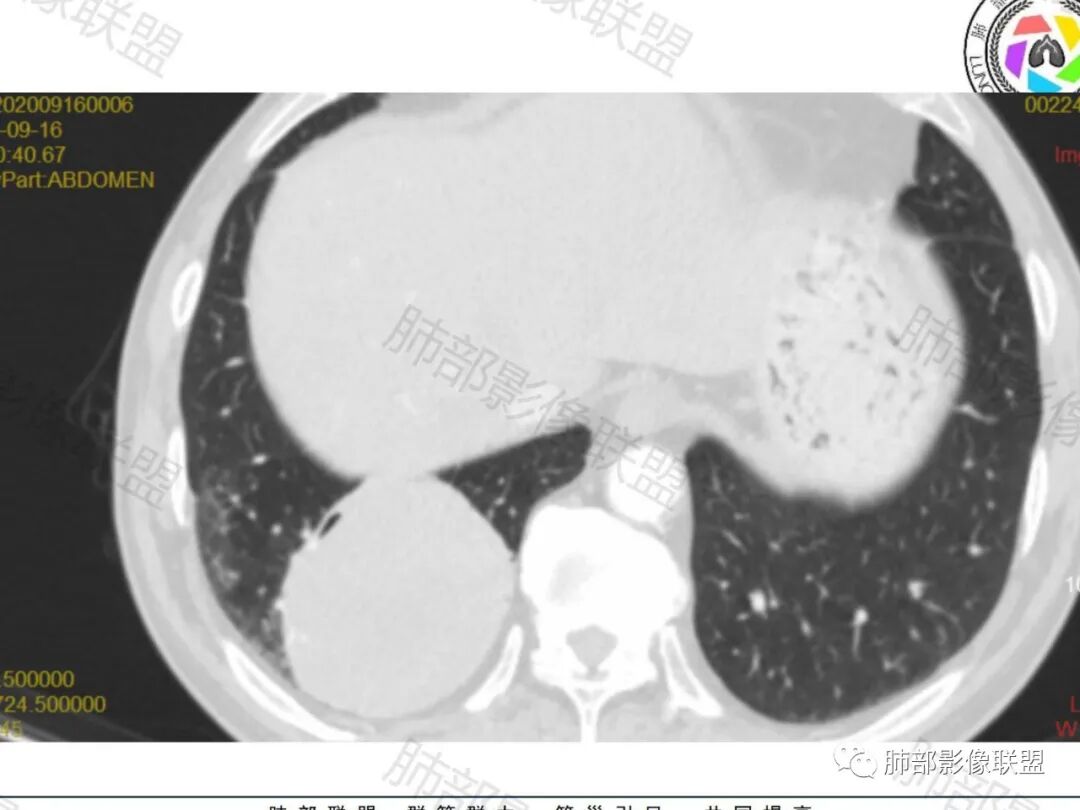

右肺下叶一类圆形肿块影,内缘边缘光滑,外缘边界模糊,可见磨玻璃影,整体以彭隆为主,部分边缘包绕支气管,平扫密度尚均匀,增强后不均匀强化,部分与膈肌黏连,临床,62岁男性,无症状,考虑恶性:腺癌,鳞癌,神经内分泌癌,肉瘤

老年人,偶然发现,右肺下叶类圆形软组织占位,密度较均匀,病灶边缘光滑,无毛刺分叶,支气管血管受挤压向外移位,增强病灶强化较均匀。考虑恶性肿瘤,外向内生长,肉瘤,肉瘤样癌,癌肉瘤,其次神经内分泌癌。

老年男性,右肺下叶软组织肿物,整体外形光整,周围组织推挤,可见血管贴边,貌似又有血管进入,整体强化均匀,考虑良性可能大,硬化性肺细胞瘤?鉴别sft

老年男性,偶然发现,说明平时没有症状,边缘光整,血管贴边,整体强化均匀,倾向于良性或者低度恶性(PSP?类癌?)

老年男性,肿瘤标志物高,右肺占位,边界清楚,内部密度均匀,坏死不明显,无明显分叶,血管贴边,考虑PSP,老年男性,肿块大,需鉴别恶性,肉瘤样癌?高分化鳞癌?

男性,62,胆结石入院胸部CT偶然发现占位。肿标稍增高,右肺下叶胸膜下肿块,边缘尚清,密度较均匀,增强明显强化,血管贴边,空气新月征?静脉期可见低强化区,首先考虑PSP,鉴别肉瘤样癌及神经内分泌肿瘤

老年男性,右肺下叶肿块,边缘光整,血管贴边,部分血管进入,整体强化尚均匀,考虑大细胞癌,鉴别PSP、SFT

右肺下叶类圆形软组织肿块,病灶边缘光滑,无明显毛刺分叶,支气管受压推移,血管贴边,部分血管进入病灶,增强病灶强化不均匀,内可见低密度,病灶与右侧膈肌分界不清,考虑神经内分泌肿瘤,大细胞癌。鉴别PSP

老年男性,肿瘤标志物高,右肺下叶类圆形肿块,宽基底与胸膜相连,边缘光整,密度均匀,周围气管及血管受压推移,延迟强化,其内见纤细血管,似有小低密度灶,首先考虑间叶组织恶性肿瘤,良性平滑肌瘤、纤维瘤不除外

患者中老年男性,检查发现右下肺占位。查肺癌标记物稍有升高。血常规白细胞计数稍降低。胸部CT:右肺下叶后基底段类圆形肿块,边缘光滑,边界清楚,周边见气管受压扩张,增强轻度强化,内见点状低密度影,见血管贴边。综合考虑良性过低度恶性病变,PSP可能,其它恶性肿瘤待排。

支气管,血管均受压推移,类圆形占位,无分叶,无毛刺,光滑表面,明显均匀强化,倾向于psp,鉴别错构瘤,肉瘤,肉瘤样癌,类癌等神经内分泌肿瘤,转移,imt。

老年男性,右肺下叶软组织肿块,边缘光滑,血管和支气管贴边,肿块与膈肌分界不清,增强后不均匀强化,可见点片状低密度影,考虑良性或低度恶性肿瘤,psp,神经内分泌肿瘤

右肺下叶大肿块,血管贴边,部分小分支进入肿块内,密度略欠均匀,边缘总体光滑,支气管关系不明确,老年人,总体考虑恶性,nse高,首先考虑神经内分泌癌,鉴别肉瘤,转移瘤

右下肺大团块,边界较清,病灶内有血管影,小灶低密度,胸膜下脂肪清晰,需要薄层确定肺血管有没穿行,疾病谱:神经内分泌癌(大 类),SFT,PSP,肉瘤样癌,间叶肿瘤,考虑神经内分泌癌(大 类)>sft>psp>肉瘤样癌

老年男性,NSE高。右肺下叶软组织肿块,平扫密度均匀,增强后不均匀强化,其内似可见小血管影。肿块边缘光滑,无分叶无毛刺,血管和支气管贴边。考虑神经内分泌肿瘤,鉴别:psp

老年男性,检查发现右下肺占位。CT:右肺下叶一类圆形肿块影,膨隆,无分叶,边缘基本光滑,近端支气管推挤狭窄,与胸膜夹角为锐角,增强见不均匀强化,未见坏死,近端见血管贴边,胸壁脂肪间隙清楚。考虑良性病变——PSP可能性大。鉴别神经内分泌癌、肉瘤、SFT。

右肺下叶软组织肿块,边缘光滑,临近血管受压变形且增粗,增强后见斑片状低强化区,界不清,实性部分见条状血管影,边缘光滑,考虑PSP可能,肿块与支气管关系不密切,腺癌,腺鳞癌不符合,肿块内增强后血管走形自然,间叶组织起源肉瘤不符

有意思的病例,男性,右肺下叶肿块,强化中等,血管贴边,肿标高,考虑低度恶性肿瘤,神经内分泌肿瘤,类癌最可能,别的感觉都要往后放,PSP,我三十五例病例,男性只有3例,比例太低了,而且强化幅度也偏低,而且肿瘤标志物好几个高的,只敢放第二位了

右肺下叶肿块,呈外带大内带小的椭圆形改变(内带受支气管及血管挤压原因),边缘光滑,无分叶毛刺,支气管受压,增强后,均匀延迟强化,动脉期见血管贴边,静脉期内部瘤样血管强化区,相邻胸膜无侵犯,纵隔无淋巴结肿大,符合PSP,不鉴别。

老年男性,肿瘤标志物高,右下肺占位性病变,密度均匀,其内无明显坏死,均匀强化,无毛刺分叶,考虑硬化性肺细胞瘤,鉴别肉瘤样癌

老年男性,右肺下叶肿块,边界光滑,血管贴边,部分小分支进入,肿块内可见增粗血管,肿瘤指标偏高,总体考虑恶性,不典型类癌?大细胞癌?鉴别PSP。

胸部CT:右肺下叶一类圆形肿块影,边界清楚,大部分边缘光滑、外缘边界模糊,邻近支气管推移、血管贴边,病灶内可见分枝状血管,平扫密度尚均匀,增强后大部分均匀延迟强化,部分与膈肌黏连、尾征?考虑:类Ca>PSP>SFT。鉴别肉瘤样Ca,CD等。

肿块位于周围(起自细支气管呼吸道上皮),均匀膨胀生长(符合良性的生长特点),病灶内部大部分密度较均匀,部分小低密度不强化区(囊变),增强强化较明显,边缘血管增粗贴边,临近支气管受压,支持PSP。